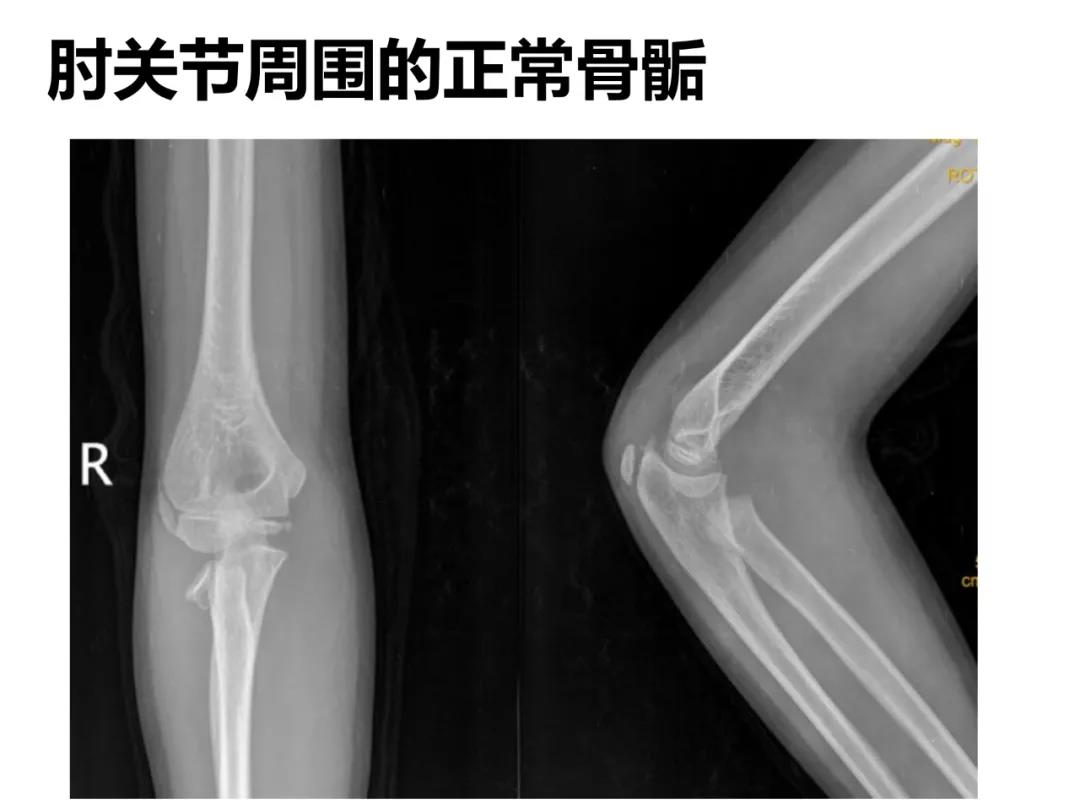

小儿骨科X线片汇总,临床读片宝典!